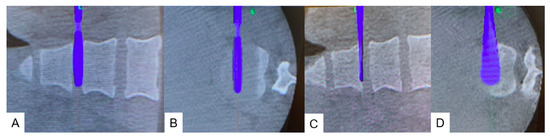

2.4.2. Posterior Osteotomy